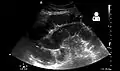

- Small bowel obstruction on ultrasound[19]

Small bowel obstruction on ultrasound[19]

Radiological signs of bowel obstruction include bowel distension and the presence of multiple (more than six) gas-fluid levels on supine and erect abdominal radiographs. Ultrasounds may be as useful as CT scanning to make the diagnosis.[17]